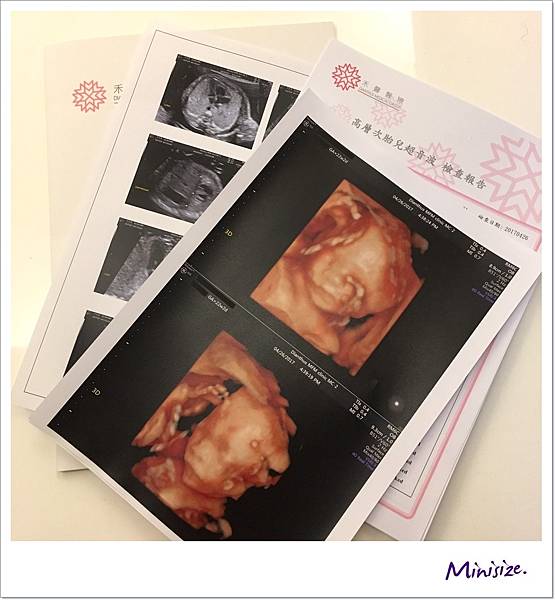

進入高層次超音波檢查吧

高層次超音波為2D檢查

建議安排在妊娠的2024週進行

此時寶寶大小羊水量最為適中

週數太小,有時胎兒心臟血管影像細節會比較不清晰

週數過大,因胎兒骨頭鈣化越來越明顯,遮擋了在骨頭後的影像

加上胎兒活動空間變小,姿勢不佳則會增加檢查的困難

我們在一個月前預訂禾馨民權婦幼診所自費做高層次超音波

22週時特別請了一天產檢假前往進行檢查 費用4200

不得不稱讚禾馨醫療的環境真的很棒

陪同孕人檢查的親友

可以在診間舒適的沙發上一同看著牆上螢幕研究寶寶

我選取幾張比較有趣的超音波照片解說就好

脊椎

骨骼要呈現排列整齊相互對稱

背部皮膚的表層也要光滑 完整連接

腦

箭頭處為透明中膈要明顯

左右腦也要對稱

面

一直很期待看到寶寶的長相

究竟是像爸爸還是麻麻?!

爸媽綜合體又會呈現什麼樣子

也許寶寶想保留一點神祕感

這是唯一張好好配合拍照的

大大的鼻子、嘴巴好福氣!!

還記得前面提到 會有兩次醫療人員操作儀器檢查嗎?

技術師只捕捉到一張寶寶正面照

其他因寶寶姿勢的關係

技術師交棒給醫生的時候也有特別註明

醫生快速地全項目檢查一輪後

將之前未完成的部分也足一補齊

我們又再度回到胎兒的正臉

此時寶寶跟我們玩起遊戲來了

頑皮寶寶:手手、 臍帶 一起遮住臉臉不給你們看

寶寶:我累了

你們照太久 我先抱著腿腿入睡囉

超音波結束後

醫生會先至旁邊諮詢室等待

等我們都到齊後

電腦開啟報告再次解說此次高層次檢查結果

我們的Timo寶寶檢查數據都正常 很健康唷!

紙本的報告

報到櫃檯也會立即印出彩色版本

離開前別忘記領取喔